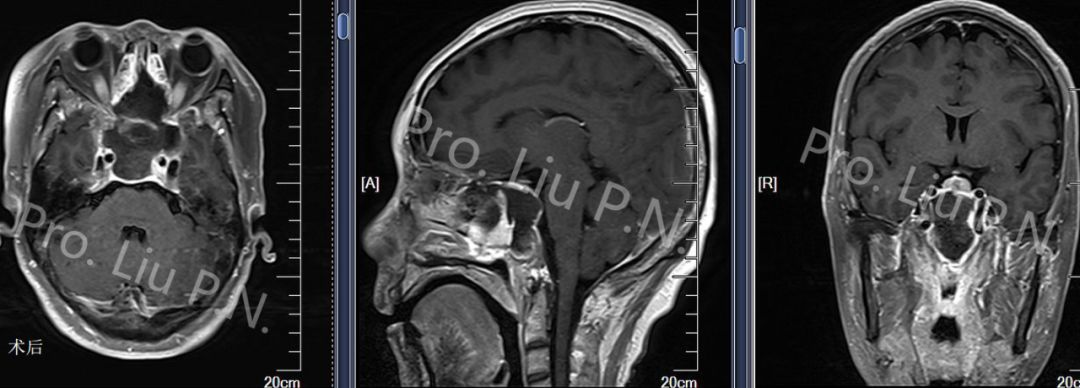

六、扩大经蝶窦入路手术案例

--侵袭性垂体瘤

![]()